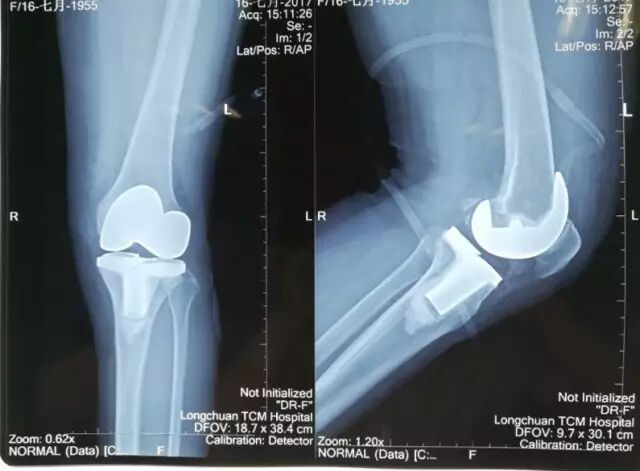

↑图:术后拍片情况